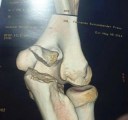

There’s no denying we’re broken. Financially (yes, that’s old news), in spirit (from bad to worse on the pitch) and, as of yesterday, also in regard to Prass’ right elbow: our keeper fractured it and underwent surgery yesterday (Monday) night. Pre-surgery, Prass posted an x-ray of his elbow on instagram. The forecast? Some three months of recovery…